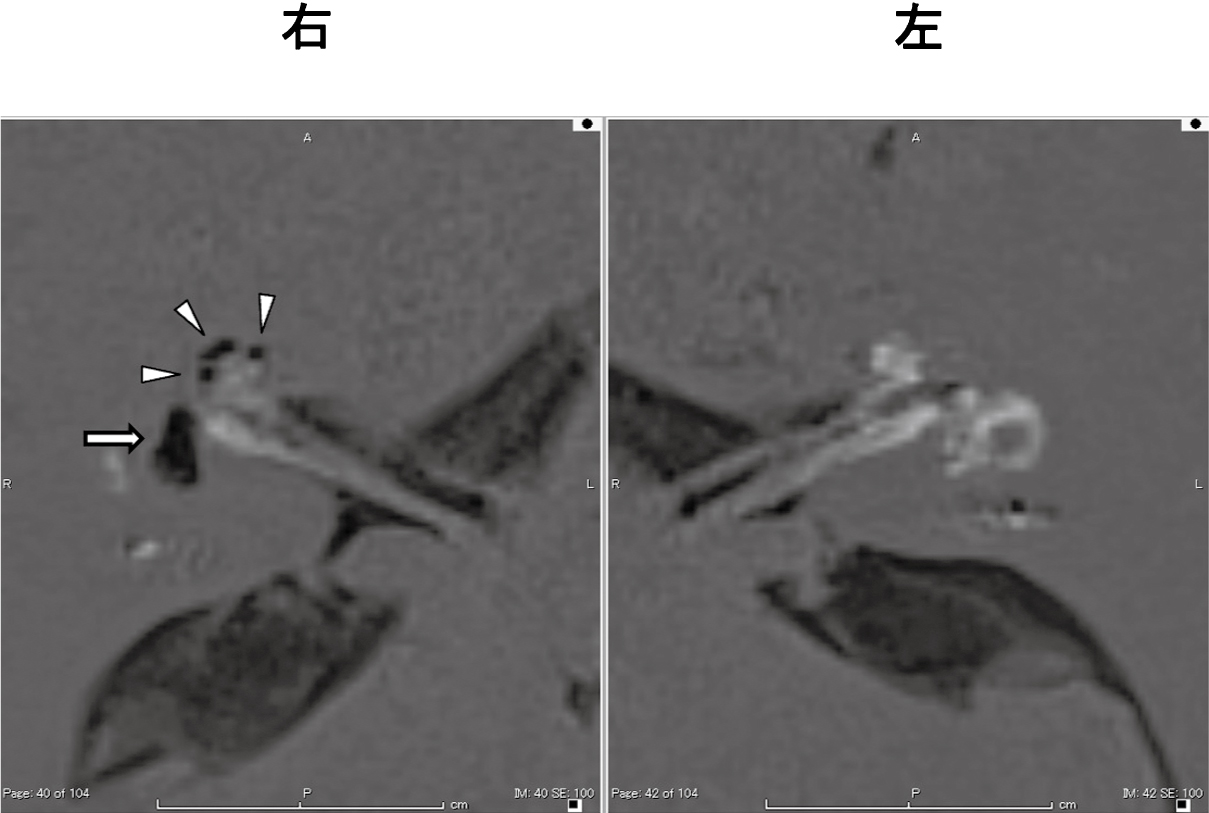

めまい発作が落ち着いてきた段階で改めて本人に確認したところ,「思い返すとめまい発作時から左耳閉感があったようにも思う」とのことであった。さらに退院後(入院から28日目)に施行した内耳造影MRI(HYDROPS法)を施行した(通常量のガドリニウム造影剤を静注し4時間後に撮像。撮像条件:Siemens社製MAGNETOM Skyra,3.0T,ヘッドネックコイル20 channel,反転時間は外リンパ陽性像2050 ms,内リンパ陽性像2250 ms)8)。結果,聾側である右側のみ内リンパ水腫が示唆され(図5),左側には内リンパ水腫は示唆されなかった。以上の所見より今回の入院時のめまい発作は左耳に生じた対側型DEHではなく,突発性難聴を含めた左側の急性前庭蝸牛障害によるものであったと診断した。

本症例では,現病歴に提示した今回のめまい発作での入院時,その病態について当初は過去の経過と同じくDEHによるめまい発作の可能性を考えた。入院後の検査所見を表1にまとめた。良聴耳側の聴力低下および前庭蝸牛機能低下を認めたため対側型DEHの可能性を考えたが,cVEMP tuning property testでは左右ともに内リンパ水腫は示唆されなかった。さらに内耳造影MRIでの内リンパ水腫評価を行ったところ,聾側にのみ著明な内リンパ水腫を認めた。Fukushimaら18)は,DEHにおける内耳造影MRIでの内リンパ水腫所見について,同側型DEHでは聾側に明らかな水腫がみられ,対側型DEHあるいは両側例では左右とも水腫が見られその程度に差が無かったと報告している。また一側聾の症例において,DEHを発症している例と発症していない例で蝸牛,前庭共に明らかに内耳造影MRIでの水腫陽性率に差があったとしている4)。自験例では内リンパ水腫所見に明らかな左右差があり,したがって今回の良聴耳側の前庭障害は内リンパ水腫による可能性は低いと考えた。良聴耳にみられた聴力閾値上昇については,高音域に限定されているものの5年前との閾値差がそれなりに大きかった。実際の患者自身の自覚は,めまいが軽快した後に本人に問いただして初めて「耳閉感があったように思う」という程度で聴力変動との乖離が感じられるが,強度のめまい発作の最中であったため認識できなかった可能性もある。前回検査から5年が経過する間にいくらかの聴力低下が進行していた可能性も否定はできないが,年齢を考えると加齢性変化での説明は難しい。また渉猟し得た限り,対側型DEHとされる症例で高音域のみの難聴を来たした症例の報告はなかった。高音域の難聴がある例でも同時に低音域に難聴のある報告が多く,高音域の進行性難聴を認めた対側型DEHの報告でも全音域に難聴が見られていた19)20)ことから,本例の聴力像も積極的に対側型DEHによるものと考えるのは難しい。総合的に,今回のめまい発作は良聴耳側に生じた,突発性難聴を含めた一側急性前庭蝸牛障害によるものであると考えられた。しかし同時に,発作後1年にわたり再燃がないものの,聴力像も含めて対側型DEHやメニエール病を完全に否定することは難しいとも考えられ,今後の経過観察が重要である。

| 内耳造影MRI |

著明な前庭,蝸牛の水腫を認める |

水腫認めず |

同側型DEHの経過観察中に,良聴耳側の前庭蝸牛機能低下を伴うめまい発作を生じた例を経験した。内耳造影MRI検査で聾側にのみ内リンパ水腫を認め,対側型DEHではなく,良聴耳側に生じた急性前庭蝸牛障害であったと診断した。